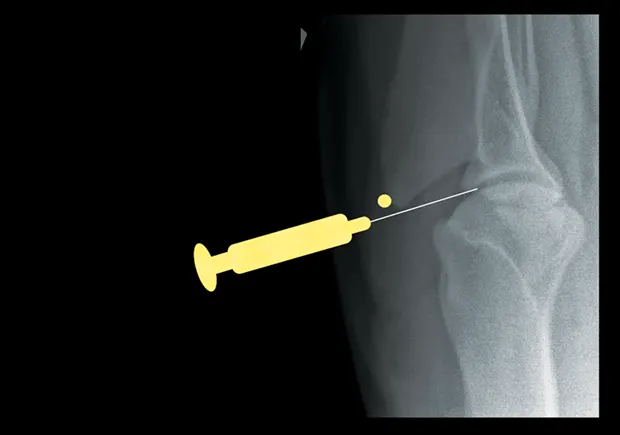

Elbow

With the patient in lateral recumbency and the affected elbow downward, place a rolled towel beneath the elbow. Apply valgus stress on the joint over the towel to open the medial side of the elbow. For large-breed dogs, insert the needle 1.5 cm distal to the medial epicondyle in a medial-to-lateral direction. The caudolateral pouch of the joint is an alternate site; however, marked effusion must be present for successful arthrocentesis.

Craniocaudal view of elbow. Insert needle about 1.5 cm distal to the medial epicondyle (yellow dot) in large-breed dogs.